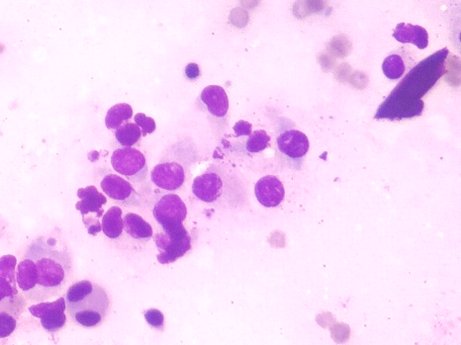

細胞診

細い針で腫瘍の細胞を採取し、染色を行ったあと顕微鏡で細胞の形態を検査します。